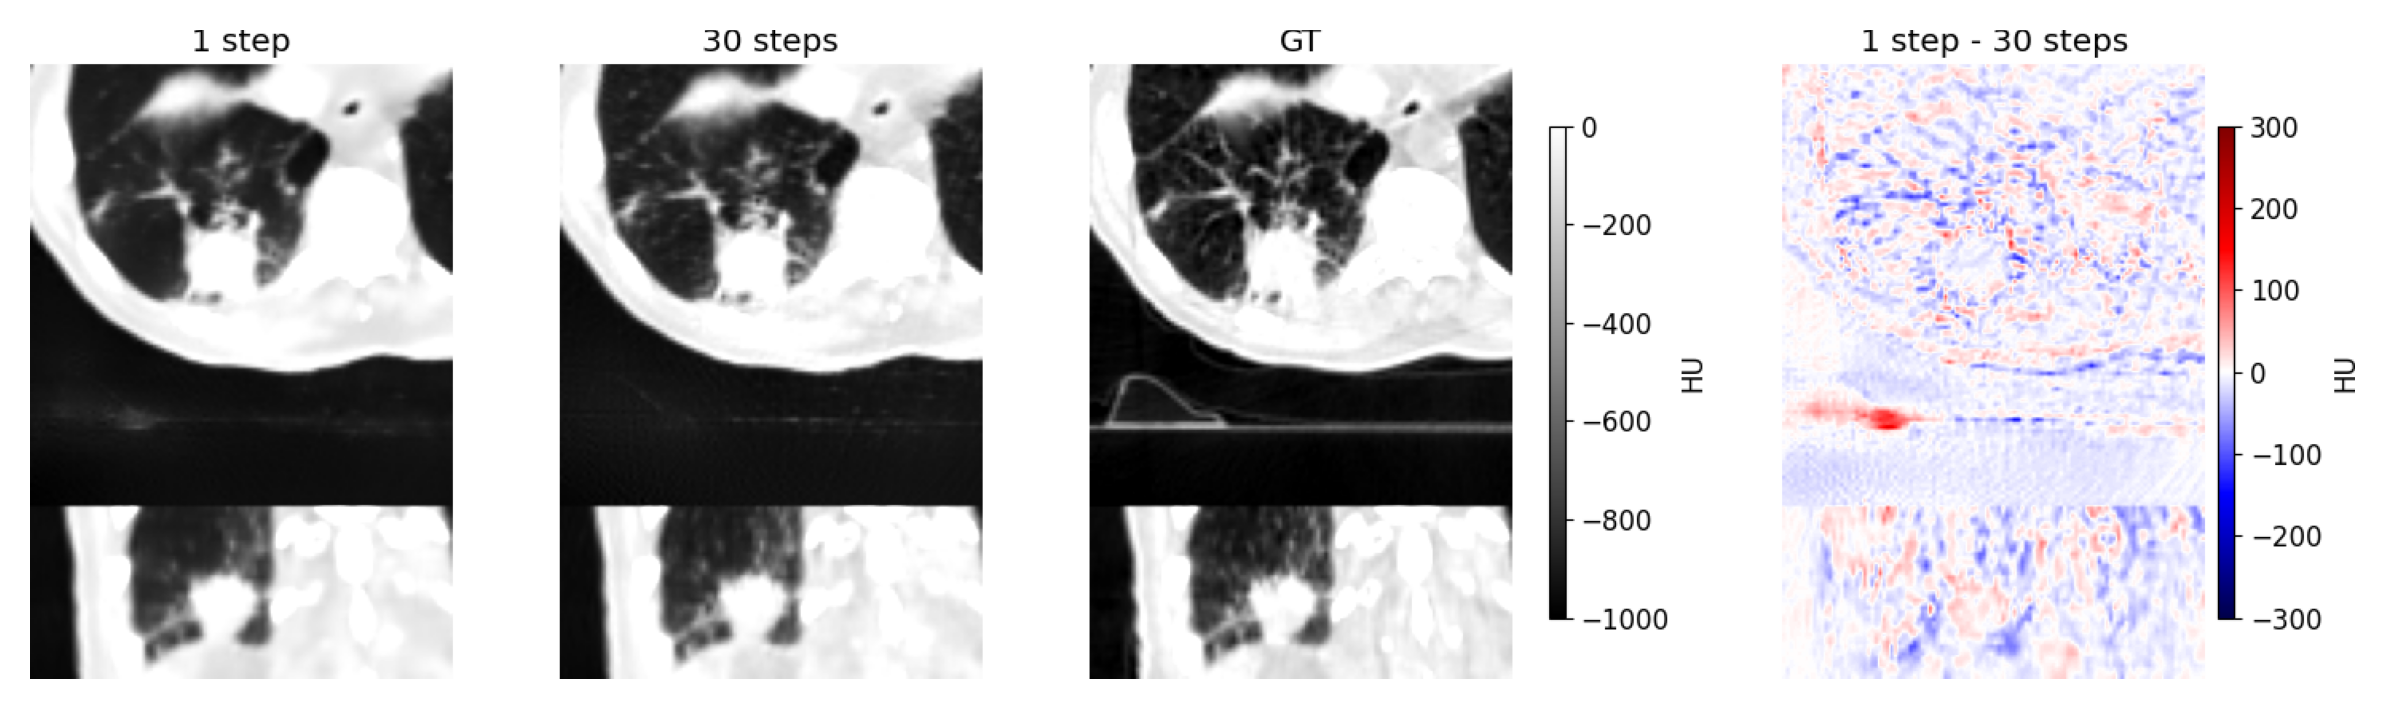

We analyse the perception-distortion trade-off in MInDI-3D through progressive sampling (Figure 3). A single sampling step yields suboptimal results, failing to optimise either metric. Increasing steps beyond 2 (2-10 steps) trades distortion for realism: PSNR declines modestly (from 33.61 dB to 33.31 dB) while perceptual quality improves (FD DINOv2: from 75.83 to 20.14). This demonstrates that MInDI-3D enables controlled trade-offs between fidelity and realism through step adjustment. Visual examples of this trade-off for a lung tumour are shown in Figure 4, where added steps enhance sharpness and detail. The optimal amount of sampling steps for fidelity, varied across images and anatomic sites.

Refer to caption

Figure 4: Comparing the MInDI-3D prediction of a lung tumour (lower right lung lobe) from a sparse 50 reconstruction with 1 vs. 30 steps (the ground truth and the difference of step 1 - step 30 as reference). There is an increase of sharpness and detail from step 1 to step 30